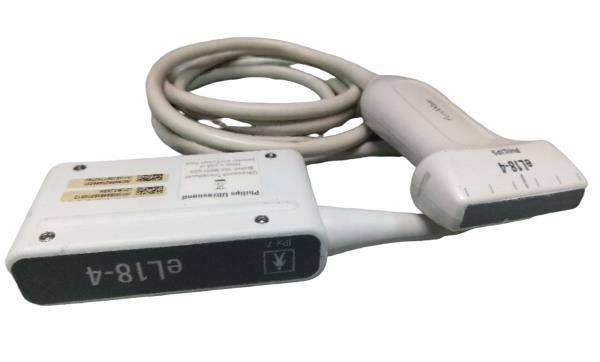

SAMSUNG HM70A PORTABLE ULTRASOUND WITH 2 PROBES

Sale price$ 11,150.88